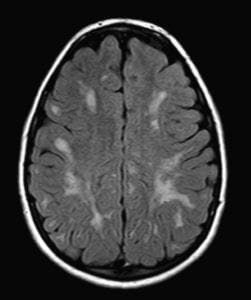

In particular a problematic one is brain MRIs like this one:

See the white patches?

They are called white opacities and are very common.

Their importance is contentious in the medical industry so your GP might not have any issue with them.

But in the insurance industry, they can cause severe difficulty in terms of getting serious illness cover.

Stephen stressed that he wasn’t saying you should try and get cover before your MRI.

Because at that stage it’s too late.

Instead buy critical illness cover long before your GP has any reason to send you for such a screening.